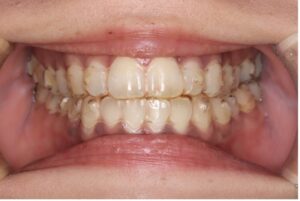

マウスピース矯正は透明の装置を歯にはめて歯を動かす方法です。

目立ちにくく、自身で取り外しができることが特徴です。

取り外しが可能なため普段と変わらず食事ができる、歯磨きがしやすく虫歯や歯周病のリスクを抑えやすいという点が魅力です。

だだし、裏を返せば外せてしまうということがデメリットでもあります。

1日20〜22時間装着する必要があるため、外している時間が長いと歯は動きません。

自己管理がポイントになってきます。

〈メリット〉

・目立ちにくい

・取り外しができるため口腔内を清潔に保ちやすい

・口内炎ができにくい

・ワイヤー矯正より通院回数が少ない(1〜2ヶ月に一回来院)

〈デメリット〉

・自己管理が必要

・症例によってはワイヤー治療を併用することがある